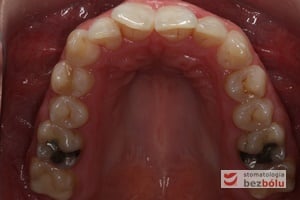

Pacjentka lat 22 zgłosiła się do naszej placówki celem podjęcia leczenia ortodontycznego. Głównym oczekiwaniem pacjentki była poprawa estetyki uśmiechu oraz brak ekstrakcji zębów na drodze do jej uzyskania. Ze względu na liczne stłoczenia zębów w górnym i dolnym łuku, dość duży materiał zębowy w porównaniu z bazą kostną, a także zgryz przewieszony boczny prawostronny po dokładnej analizie cefalometrycznej oraz analizie modeli diagnostycznych zastosowano leczenie bezekstrakcyjne z wykorzystaniem strippingu jako alternatywy dla usuwania zębów, mającego na celu uzyskanie miejsca w łuku na uszeregowanie zębów. Po fazie aktywnego leczenia trwającego 18 miesięcy zastosowano leczenie retencyjne w postaci szyny retencyjnej w łuku górnym oraz retainera stałego w łuku zębowym dolnym klejonego od kła do kła.